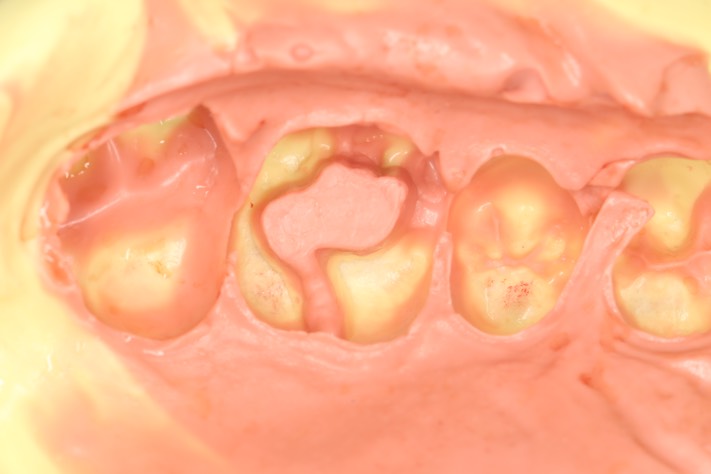

Alan Chinn #14 impression